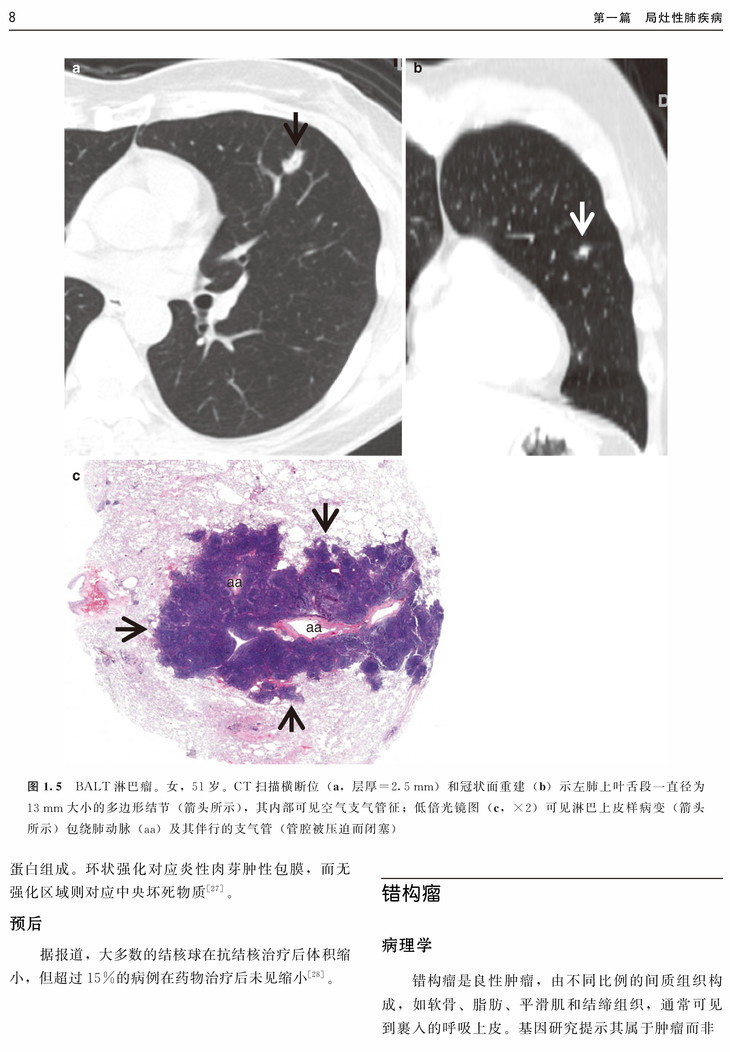

本书以常见肺部病变的CT征象为切入点,从病例入手,涵盖了肺部常见病的组织病理学、临床表现、CT表现、CT-病理对照及预后,并对每类CT征象进行了鉴别诊断总结。